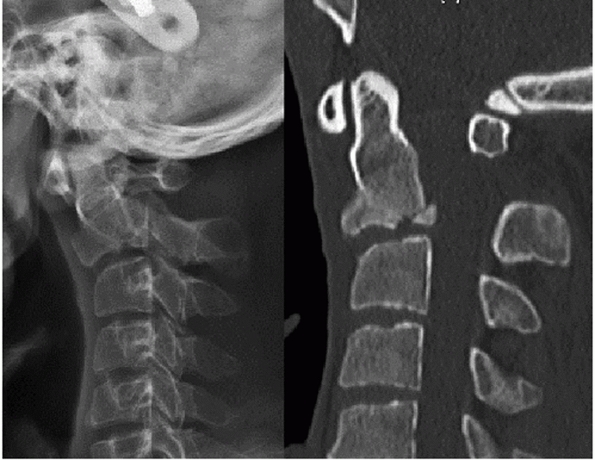

should be noted. Prevertebral swelling can be detected by assessing the

soft-tissue shadow thickness anterior to the vertebral bodies (Fig. 42-4).

If this measures more than seven mL in front of the C2-C3 disc space or

more than 21 mL at the C6-C7 disc space, there is a high likelihood of

a cervical spinal injury.167,223

Importantly, the absence of prevertebral (retropharyngeal) soft-tissue

swelling does not reliably rule out an occult cervical spine injury, as

its reported sensitivity is only 65%.129

FIGURE 42-4 Radiographic lines, landmarks, and measurements using a lateral cervical spine film. The spinolaminar line (A), posterior vertebral body line (B), and anterior vertebral body line (C) are normally unbroken. On a perfect lateral view, the facet joints should appear as stacked parallelograms (D). The prevertebral soft-tissue shadow is measured at the C2-C3 (E) and C6-C7 (F) disc spaces. More than 7 mm at the C2-C3 and 21 mm at the C6-C7 disc is strongly suggestive of an underlying spinal injury.

|